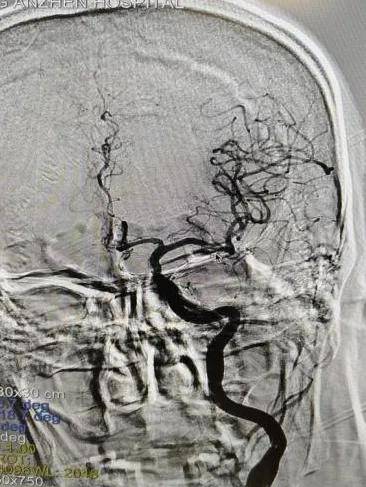

神經疾病中心急診值班醫生李明軒,憑藉豐富臨床經驗,第一時間判斷患者高度疑似急性腦卒中,影像科急診團隊完成頭頸部血管檢查(CTA),結果顯示:左側大腦中動脈M1段急性閉塞!這是給左腦供血的主幹血管,堵住了。

圖說 / 術前CTA顯示左側大腦中動脈M1段急性閉塞

圖說 / 術中大腦中動脈即刻再通